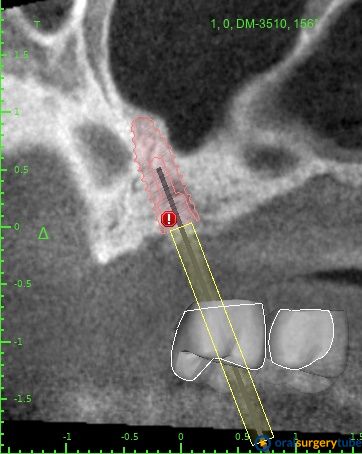

Hola compañeros, hace unos meses colgué un caso para preguntar el paso siguiente a seguir en una elevación que se ha quedado un pelín escasa. Alberto me dijo que él colocaría 2 implantes en mesial y elevaría más en la zona distal. Hoy he vuelvo sobre él, y sigo con dudas. En la zona elevada no caben 2 molares (os paso una panificación rápida en Bluesky) e incluso forzando y angulando aun así serían implantes pequeños y estrechos de 3,5x8,5 mm en hueso regenerado con bovino...no me convence...entonces:

Mi plan A sería: Jugando con la cirugía guiada me cabría un implante mesial de 4x8,5 y uno pterigoideo de 3,5x10, éste en hueso nativo 100% pero con la anatomía justita. Tengo dudas si jugar en ambos lechos usar las fresas Versha para ganar algo más de altura en el mesial y mejor condensación del lecho en ambos... O no liarla y dejarlo así como os digo sin versha.